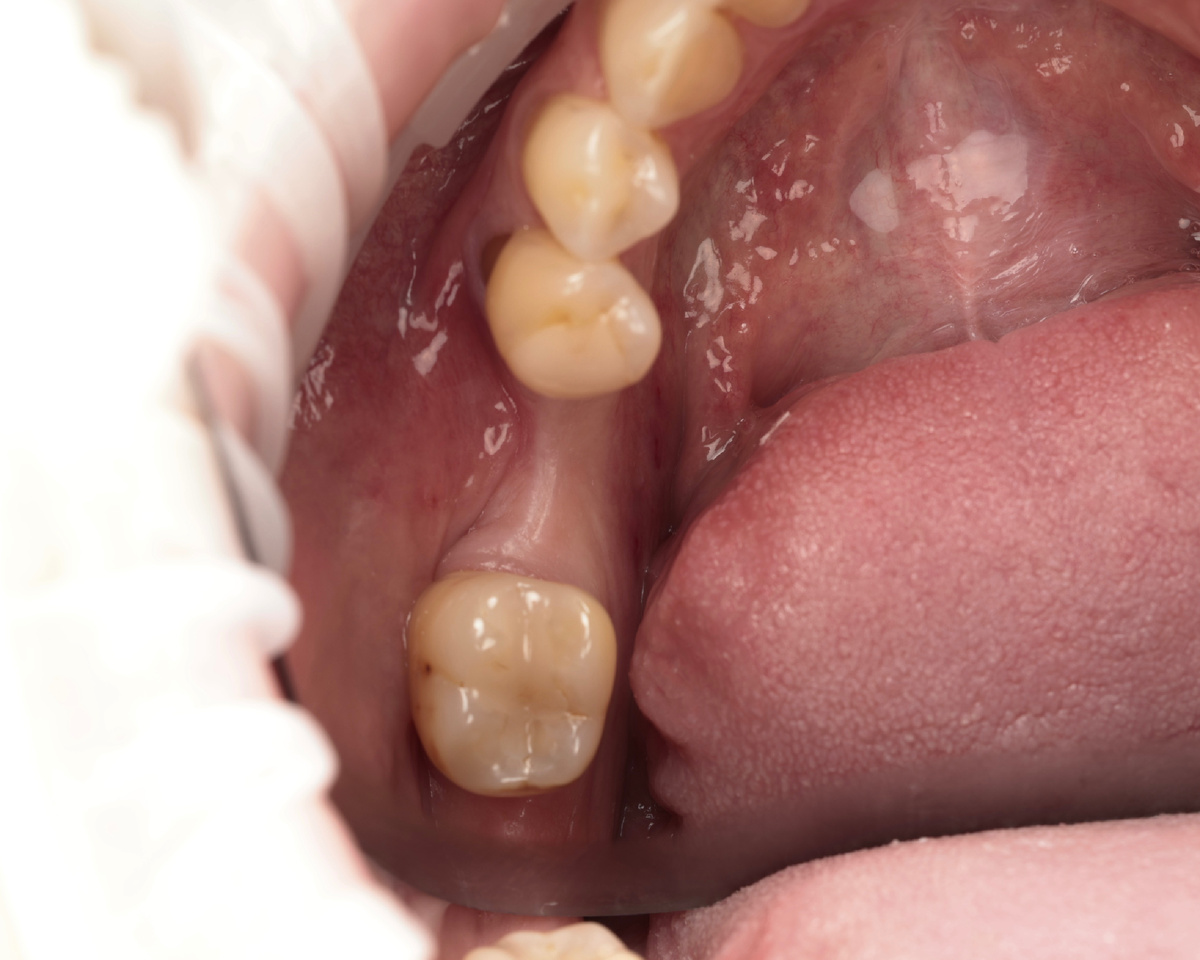

Пациент - мужчина, нужна имплантация в области 4.6 зуба (первый моляр снизу справа). Зуб удалён давно, ткани атрофировались.

Проблемная зона перед имплантацией

Из плюсов: много своих зубов, относительно стабильный прикус.

Из минусов: тонкая кость щёчно, большой дефицит десны, десна тонкого биотипа, пациент мужчина (жевательная нагрузка выше, чем у женщин).

Визуально - типичный кандидат на костную пластику. Провал такой, что имплантат ставить некуда.